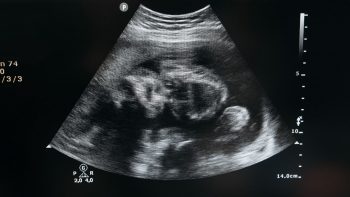

• Xác định tuổi thai chính xác bằng siêu âm (tính theo ngày kinh cuối hoặc siêu âm) — cực kỳ quan trọng để chọn phương pháp an toàn.